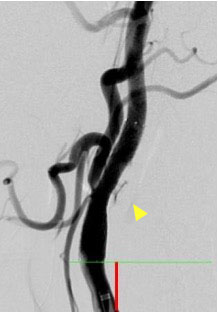

頸動脈狭窄症に対する頸動脈ステント留置術(CAS)

頸動脈狭窄症とは首の動脈が細くなる病気で,脳梗塞の原因となります。狭窄部にステントを留置することでプラークの破綻を防ぎ,脳梗塞を未然に防ぎます。ステント留置後に希釈造影剤を用いた回転撮影からMPR像を構築し,血管内腔評価を行います。

治療前

治療後